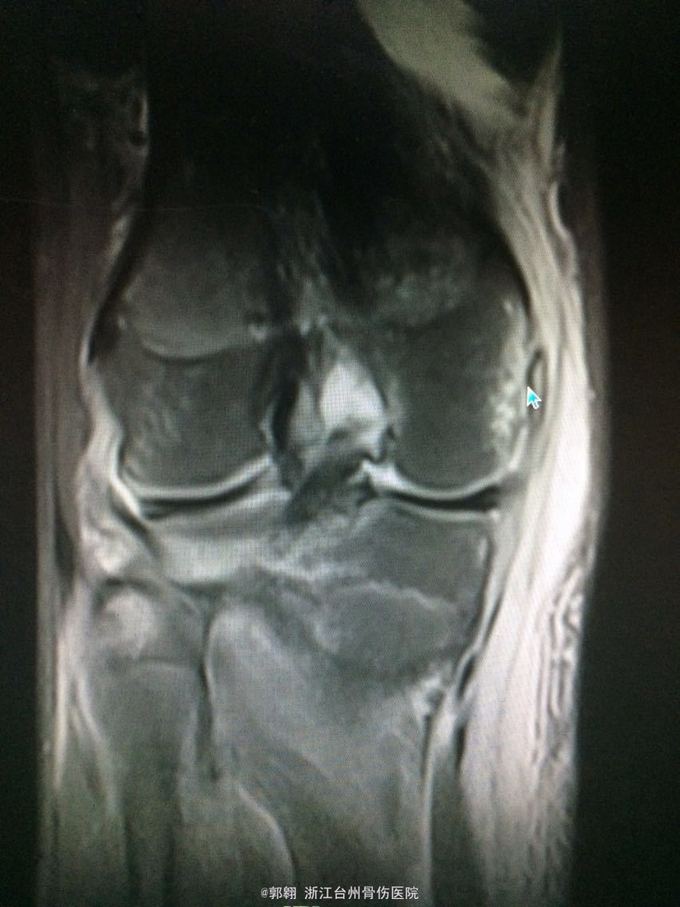

右膝关节跑步摔伤疼痛功能障碍3小时 病史:患者15岁 上体育课时跑步摔倒致右膝关节畸形疼痛 功能障碍,由老师送至医院就诊。

查体:右膝关节及小腿上段肿胀明显,张力较大,压痛位于内侧副韧带股骨处和膝关节外侧,膝关节波动感,浮髌试验阳性、扳膝试验阳性、抽屉试验阳性、Lachman阳性、膝关节屈伸活动因疼痛而障碍,足背动脉波动良好。 MRI:右膝关节股骨内髁骨折 胫骨平台外侧缘骨折

诊断:右膝关节内侧副韧带撕裂 前交叉韧带损伤 股骨内侧髁骨折胫骨平台外侧缘骨折 腓肠肌肌肉拉伤 处理:制动 支具托固定 冰敷 退肿止血药物治疗